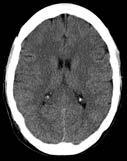

Axial non-contrast CT scan demonstrates relative hyperdensity of the cerebellum in relation to the supratentorial brain due to diffuse anoxic (absence of oxygen) injury.